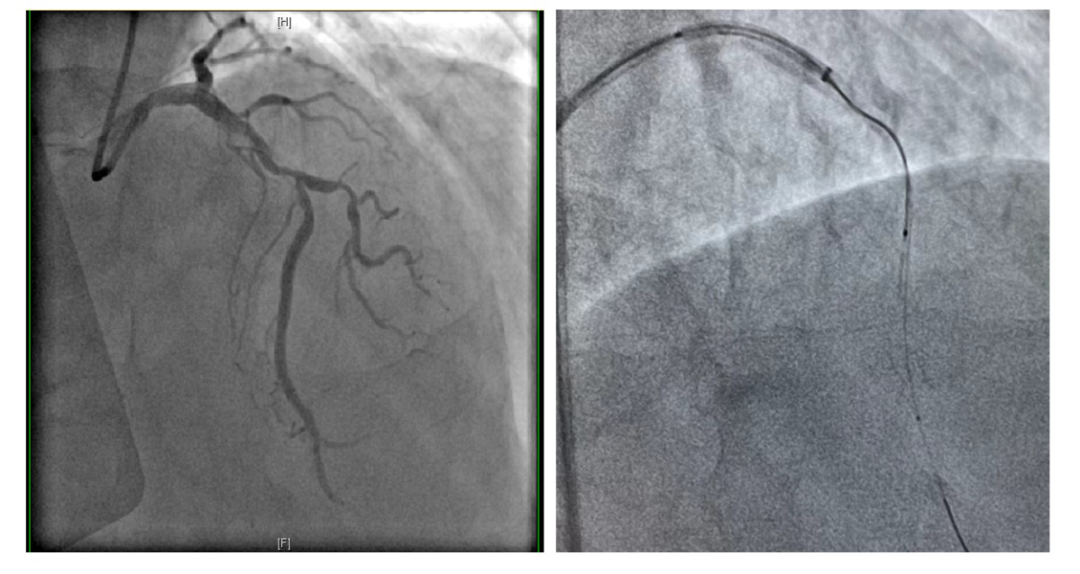

患者为一位65岁的男性冠心病患者,先期因急性心肌梗死行左回旋支介入治疗,此次造影显示,前降支近中段有重度狭窄伴有严重钙化及血管迂曲等,需要进一步介入干预。经讨论,心脏内科介入团队制订了细致的手术计划:首先通过OCT与冠脉造影融合技术,进一步准确评估冠脉钙化范围及深度,必要时采用Shockwave冲击波球囊技术方案,精确冲击冠状动脉内膜或中膜下钙化病灶后,再次使用OCT评估治疗效果并精准定位释放支架。

LAD造影提示近中段钙化严重(左)

导管支持下通过OCT导管(右)

经过充分的术前准备,6月21日,手术正式开始。术中,如术前预判,OCT检查提示患者前降支近中段多处偏心钙化及环形钙化,钙化厚度1.2mm以上,钙化严重导致多种介入器械难以通过,旋磨或激光等处理方法也难以实施,因此,在OCT及冠脉造影融合技术精准指导下,启动Shockwave冲击波球囊技术方案。